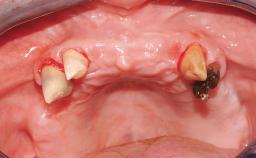

Conventional Loading of Six Implants in the Mandible and Final Restoration with a Full-Arch Metal-Ceramic FDP

A 68-year-old, completely edentulous male patient presented for evaluation and treatment options. He reported excellent general health and was taking no regular medication. He had been edentulous for approximately 12 years, having lost his teeth to periodontal disease and dental caries. The patient’s chief complaint was incompetent function. His secondary concerns included his appearance and the desire for a predictable outcome. He attributed his reduced functional capacity to his lower complete denture, which he described as poor. He was particularly concerned with the denture’s instability and poor fit. In general terms, he was satisfied with the maxillary complete prosthesis. The maxillary prosthesis was characterized by adequate retention, stability, and support, although the fit was considered less than ideal.